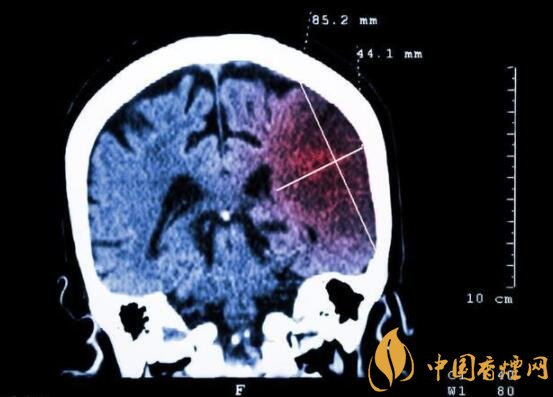

一般而言,急性腦梗塞與長期吸煙有非常密切的聯系。有長期煙齡遇到肢體活動不順,做頭顱核磁共振檢查往往查出一側大腦中動脈閉塞的可能性很高。由此可見,吸煙確實與中風存在一定聯系。